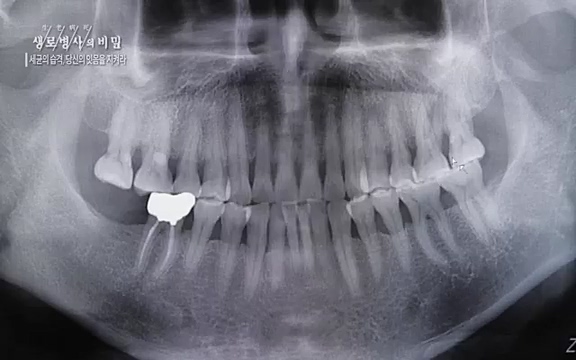

양승민 | 삼성서울병원 치주과 교수. 다른 신체 내에 있는 뼈들은 부러지면 다시 붙지 않습니까

![[792회] 생로병사의 비밀 - KBS[세균의 습격, 당신의 잇몸을 지켜라!] 감기보다 병원을 더 자주 찾게 만드는 질병이 있다. 바로 치주질환이다. 2020년 외래 다빈도 질병 1위를 차지한 치은염 및 치주질환 환자는 1,637_20220505_141151.637.jpg](https://blog.kakaocdn.net/dn/bJDahL/btrBil88rLn/l8R9GurykHvs4YjkqAOE10/img.jpg)

The probability of having cognitive impairment was 4% decreased when the number of total func tional teeth was increased, and 10% decreased when the number of total functional occlusal units was increased.

(기능적) 치아 개수 늘어날수록 인지장애 위험 4% 감소, (기능적) 교합단위 늘어날수록 인지장애 위험 10% 감소